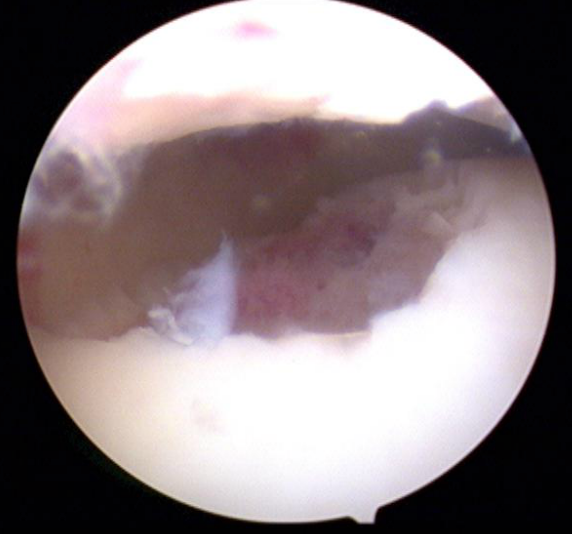

Indien nodig voert de orthopedisch chirurg een kijkoperatie van de enkel uit (arthroscopie). Via kleine steekgaatjes brengt hij een camera en werkinstrumenten in het gewricht. Het zieke kraakbeen wordt verwijderd en het onderliggende bot wordt voorbereid om het ontstane gat terug op te vullen met “litteken-kraakbeen” (fibro-cartilago).

Bij een AMIC-procedure wordt het kraakbeen- en botdefect opgevuld met eigen bot, waarna er een kunststof membraan wordt opgelijmd. Dit laat toe dat stamcellen uit het beenmerg zich in deze membraan nestelen en zich transformeren tot nieuw kraakbeen. Vandaar de (engelse) benaming: Auotologous Matrix-Induced Chondrogenesis. Het grote voordeel is dat deze techniek eenvoudig(er) is: er is geen ingreep ter hoogte van de knie nodig, en slechts zelden een osteotomie van de enkel nodig (binnen- of buitenenkel loszagen om voldoende ruimte in de enkel te creëren om deze techniek toe te passen). De resultaten van een AMIC-procedure zijn excellent.

(Met dank aan firma Geistlich voor de foto’s).